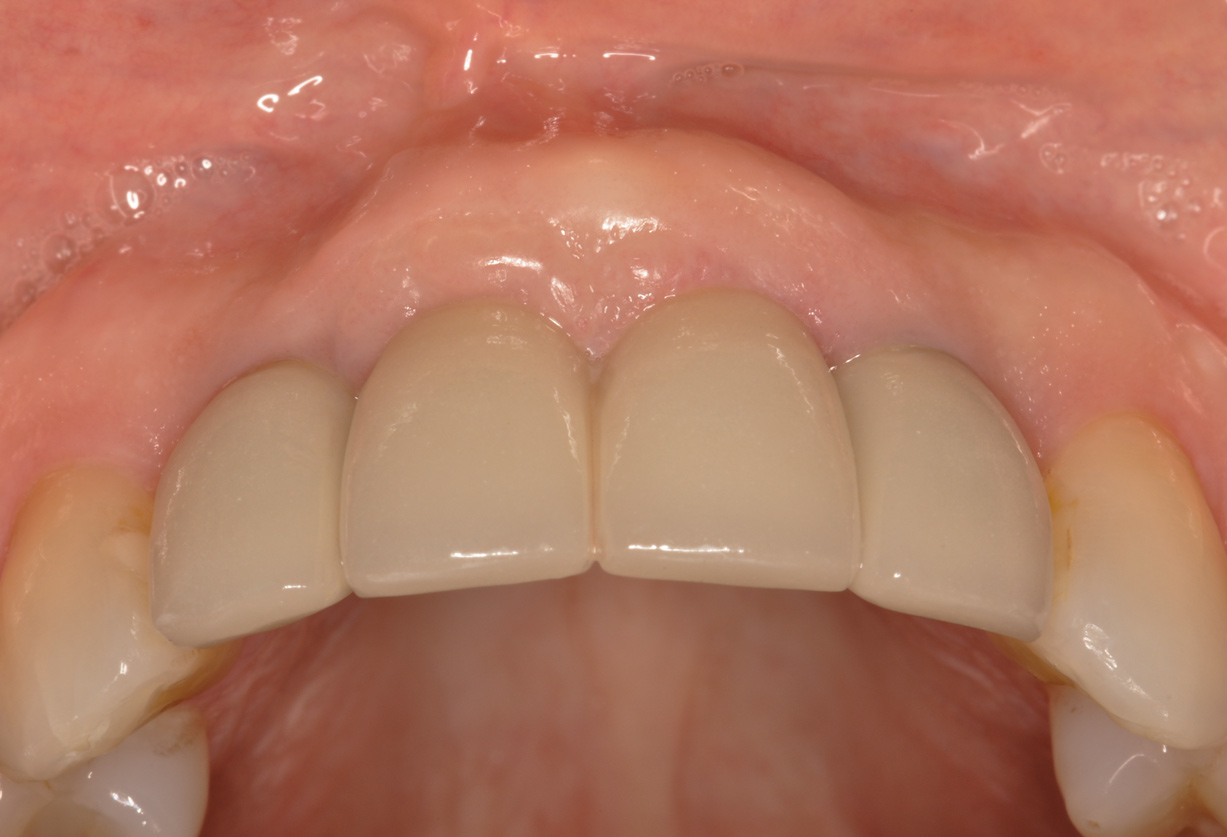

Figure 8 shows the provisionalization of No. 8 at 6 weeks postoperatively and a screw-retained provisional restoration on No. 9 to develop the subgingival transitional zone (key Nos. 8 through 10). The transitional zone will be duplicated using the custom impression coping technique. Figure 9 and Figure 10 depict the completed crowns at 5 years; implant No. 9 was screw-retained (key No. 10). In Figure 10 note the convex contours facial to implant No. 9 that are attributed to the connective tissue grafting as part of the surgical protocol creating biotype conversion from a thick to a thicker biotype. Figure 11 through Figure 13 show 5-year postoperative patient smile, periapical x-ray, and CBCT, respectively.

Fig 9. Completed crowns at 5 years, front view. Implant No. 9 was screw-retained (periodontist: Robert A. Levine, DDS; restorative dentist: Zola Makrauer, DMD).

Figure 9